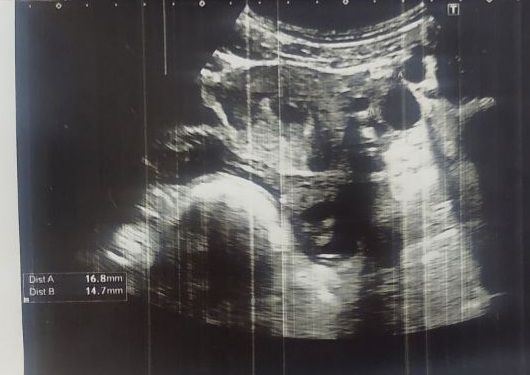

Была на 16 дц на узи.Увидели на узи кистовое образование 18 мм.Пошла к гинекологу и гинеколог сказал что это скорее всего желтое тело,но не исключил кисту. Сейчас идут слизистые желтые выделения.Кто разбираться в снимках что можете сказать?